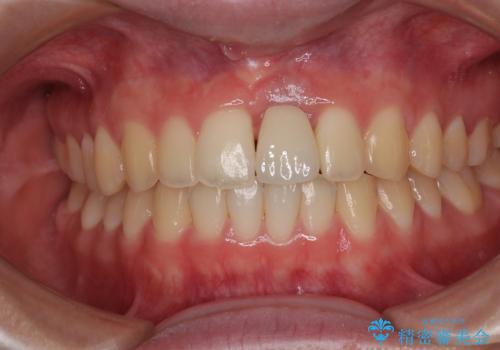

長い間歯肉が炎症を患っていたため、炎症改善後には歯肉がやや退縮した状態となっていました。

歯肉移植により歯肉形態を改善するプランも提案しましたが、十分な仕上がりとのことで、大変満足していただけました。